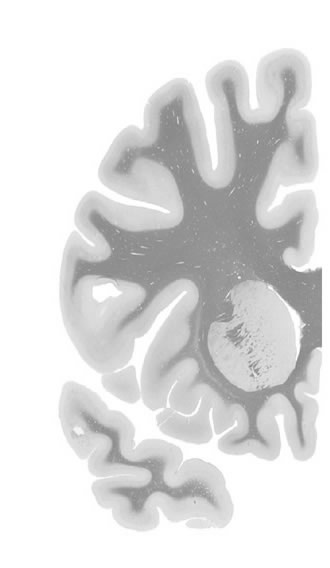

Hi-Resolution Sections · Cells (Nissl Staining) · Virtual Microscopy

Frontal sections (Nissl) from the Atlas Brain:

Macroscopy

Slice ID:

r2-0670

Plate NR:

09-10

Position:

-21,6 mm